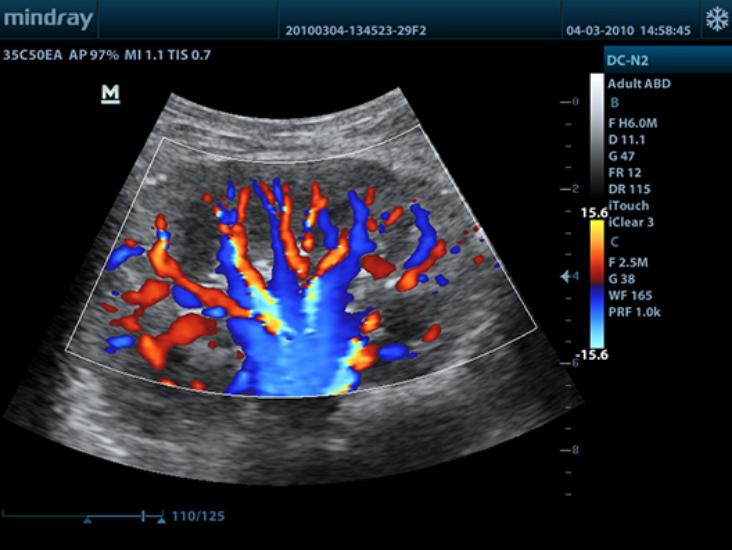

DC-N2

Color Doppler within Reach

DC-N2 offers a unique combination of relevant technology, quality and affordability. Be it an experienced ultrasound professional or a beginner, the DC-N2, with its unique self-learning software and advanced imaging technologies can be used across multiple clinical settings. With a user-friendly control panel and a user-centric workflow system, the DC-N2 can be well trusted for its performance and ease of use.

iBeam?

Permits use of multiple scanned angles to form a single image, resulting in enhanced contrast resolution and improved visualization.

Multiple Beam Formation

Maximum 4 times tasking for one transmitted beam, resulting in excellent time resolution and higher frame rate.